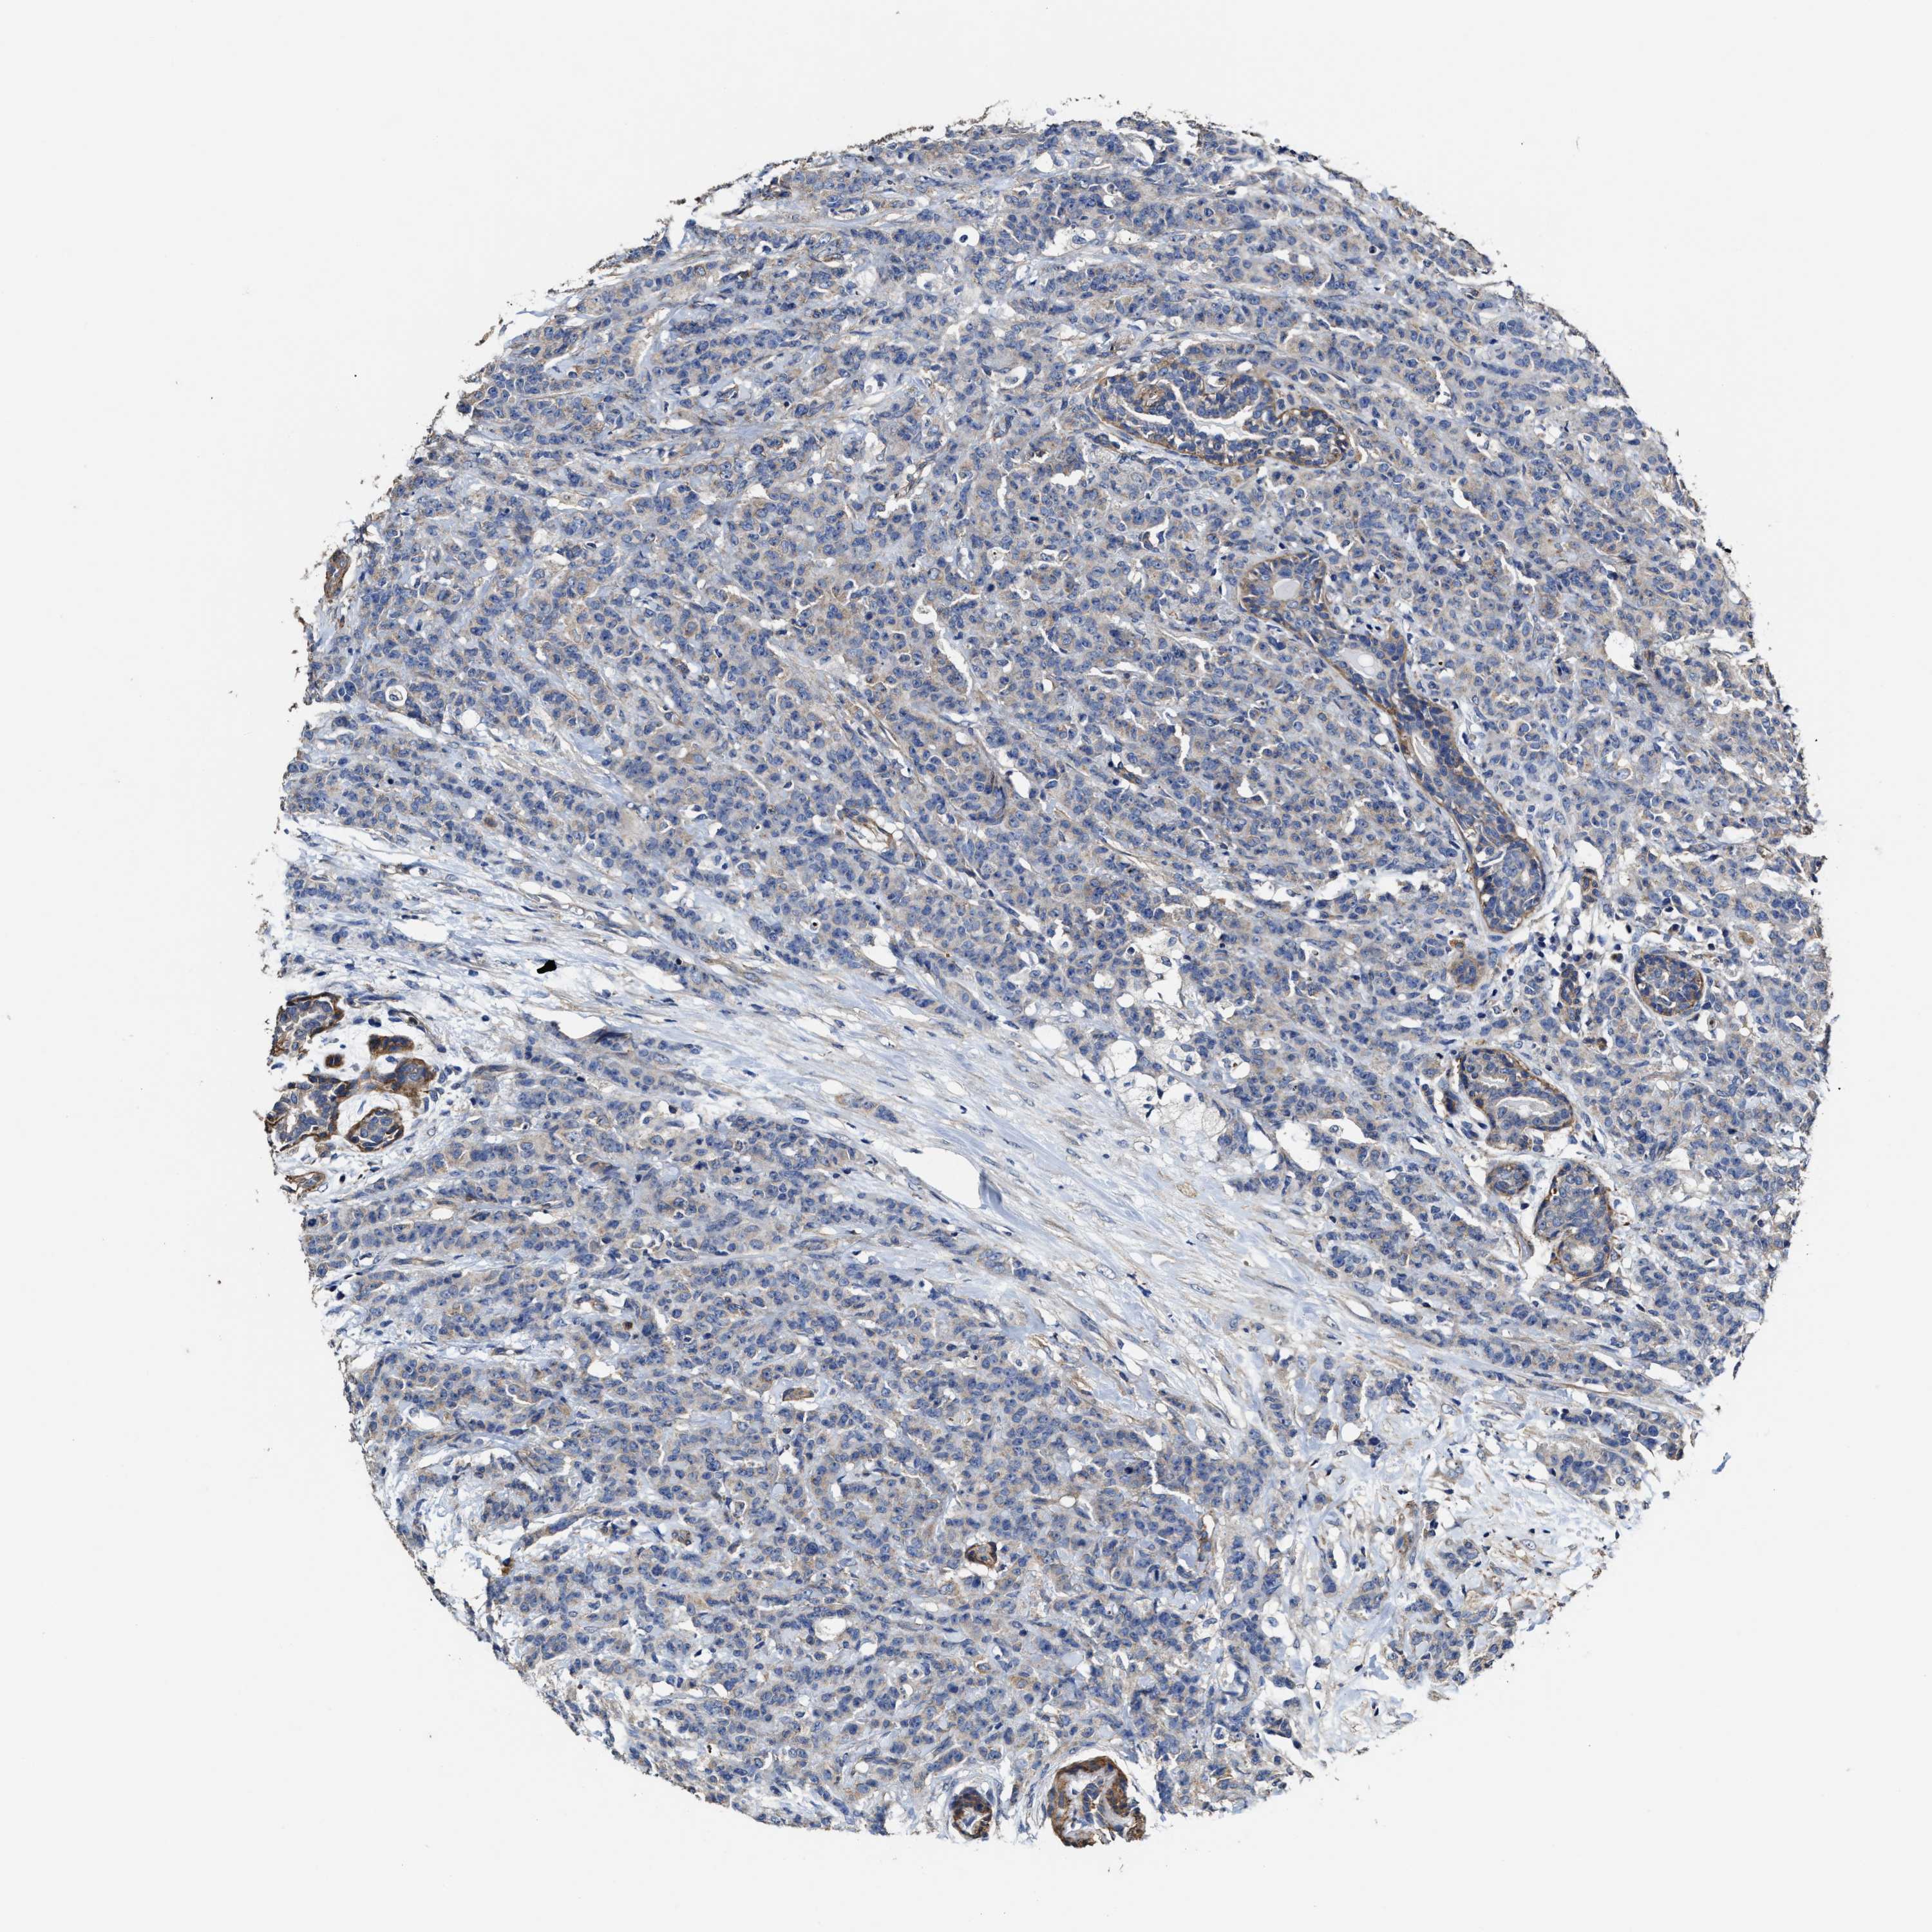

CANCER BREAST CANCER Show tissue menu

BRCA TCGA BRCA VALIDATION PROTEIN EXPRESSION

SFXN4 is not prognostic in Breast Invasive Carcinoma (TCGA)